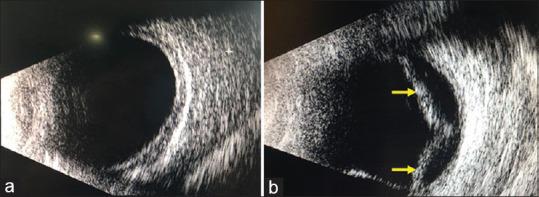

Angiotensin receptor blocker-induced bilateral ciliochoroidal effusion.

https://cdn.ncbi.nlm.nih.gov/pmc/blobs/82da/7508068/f8ba54ca21ec/IJO-68-1168-g001.jpg